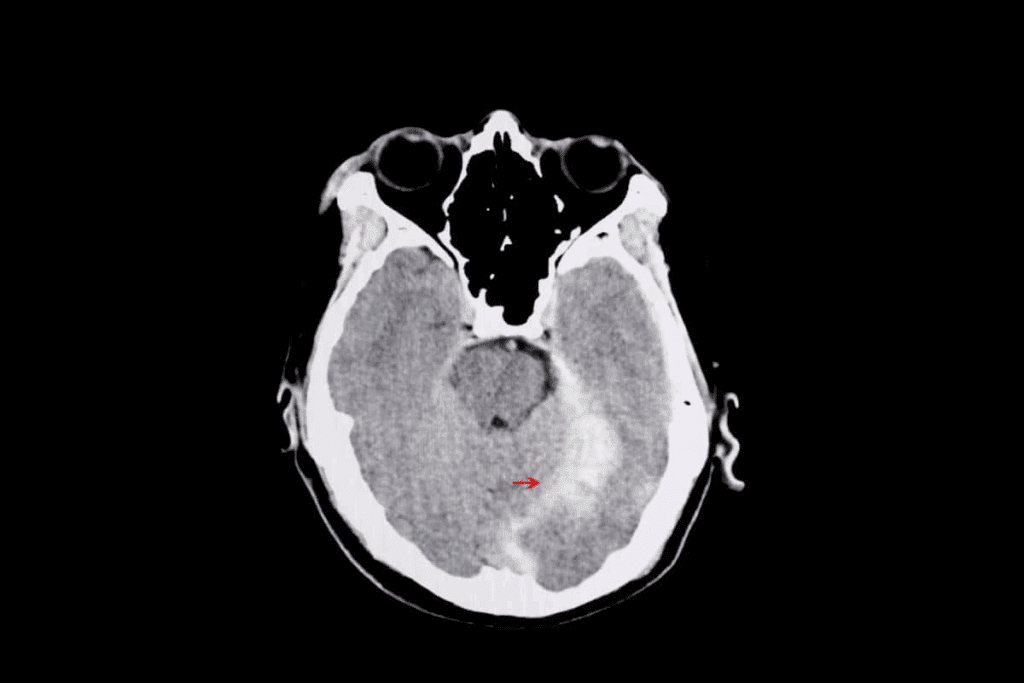

Case Studies of Rapid Progression

Many case studies show how quickly melanoma brain metastases can grow. These studies stress the need for constant monitoring and quick action to manage the disease well.

One case study showed a patient with brain metastases that grew at different rates. This case shows how complex treating these tumors can be. It highlights the need for treatment plans tailored to each patient.